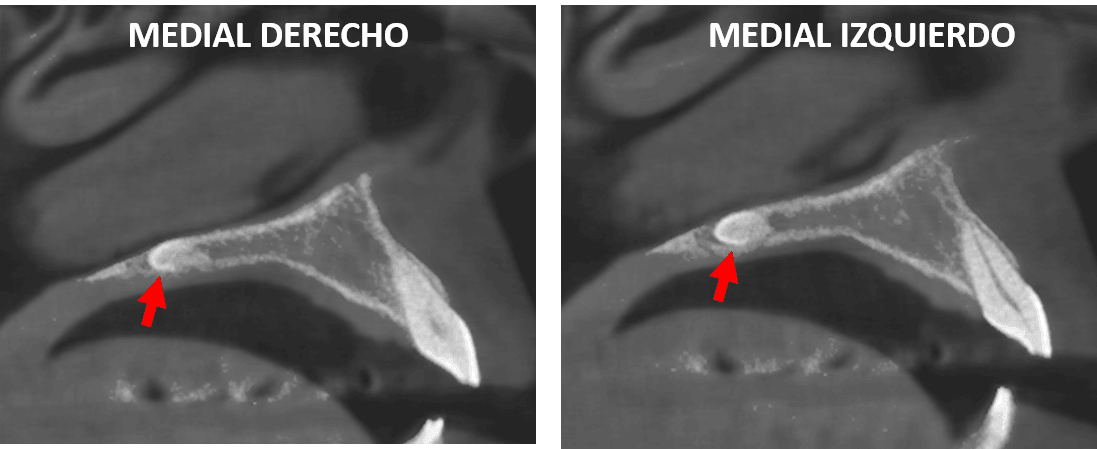

Fig.2

En cortes coronales (Fig.2) se observa que el objeto identificado en el paladar se observa orientado hacia el lado izquierdo de la zona medial, a nivel del cortical superior que compromete que compromete el piso de la fosa nasal izquierda.